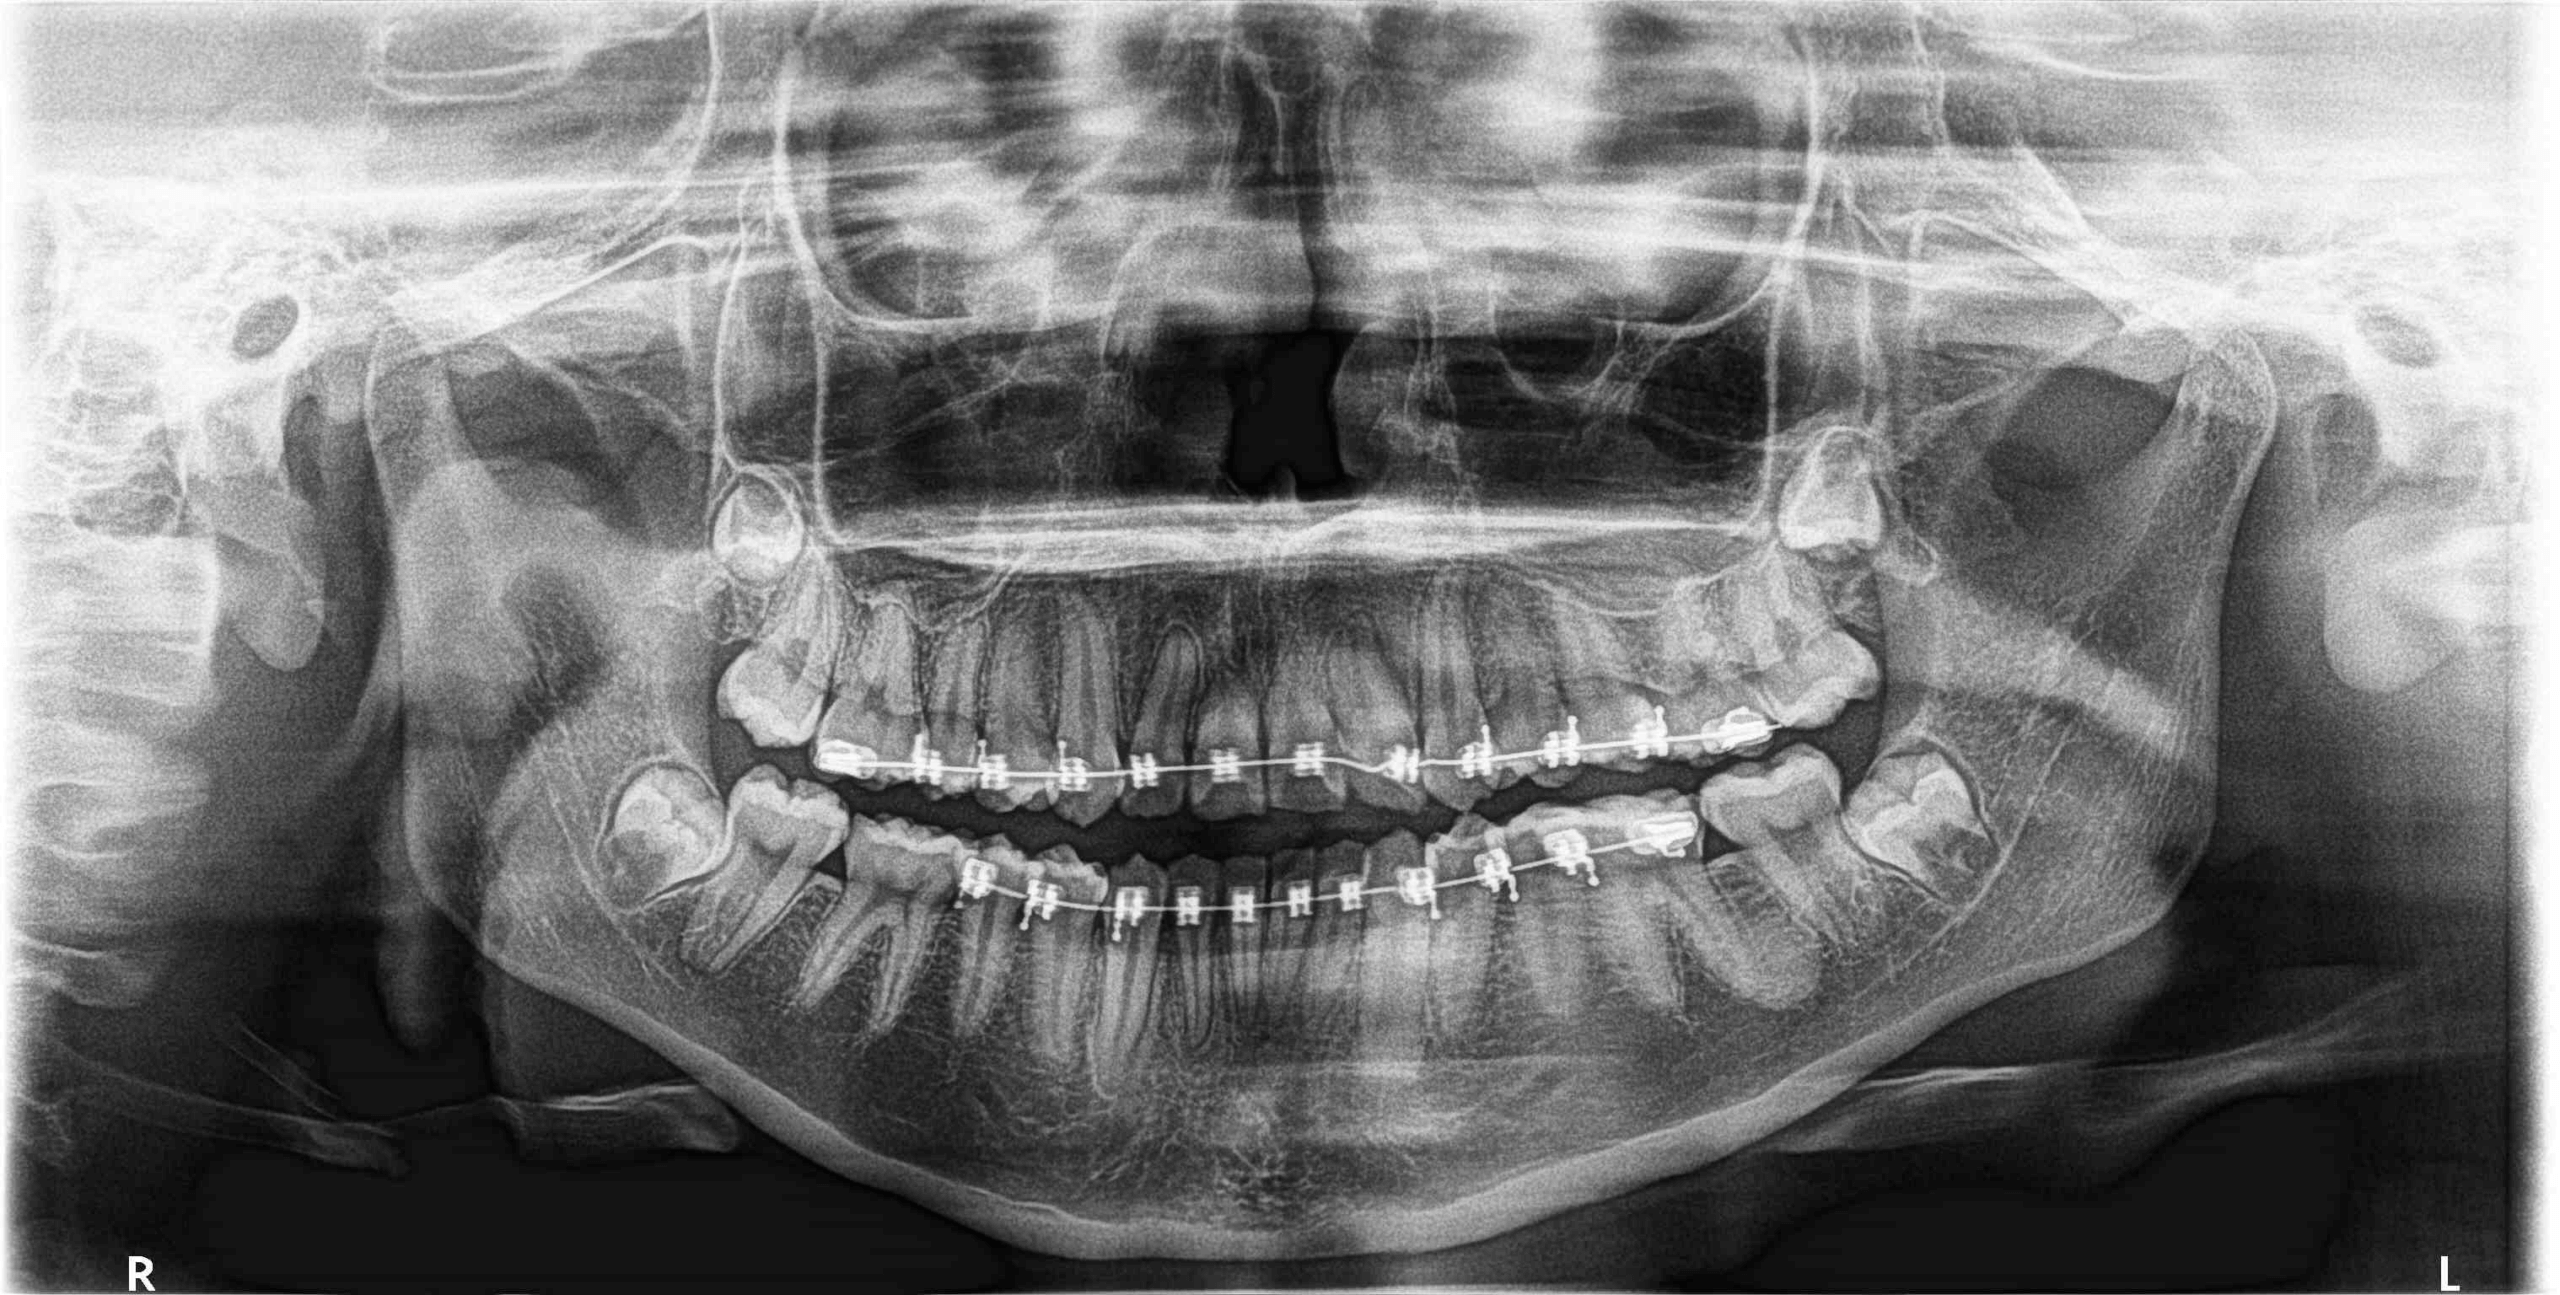

Fig.1

En la radiografía panorámica (Fig.1) se observan los terceros molares en evolución intraósea, con aparente falta de espacio para su correcta erupción, con una imagen radiopaca localizada a nivel del tercio medio radicular por distal de la raíz distal del órgano dentario 36 y la aparatología fija para ortodoncia en el maxilar superior e inferior. Se observan también el ensanchamiento del espacio periodontal de los órganos los incisivos laterales superiores y de los incisivos inferiores.